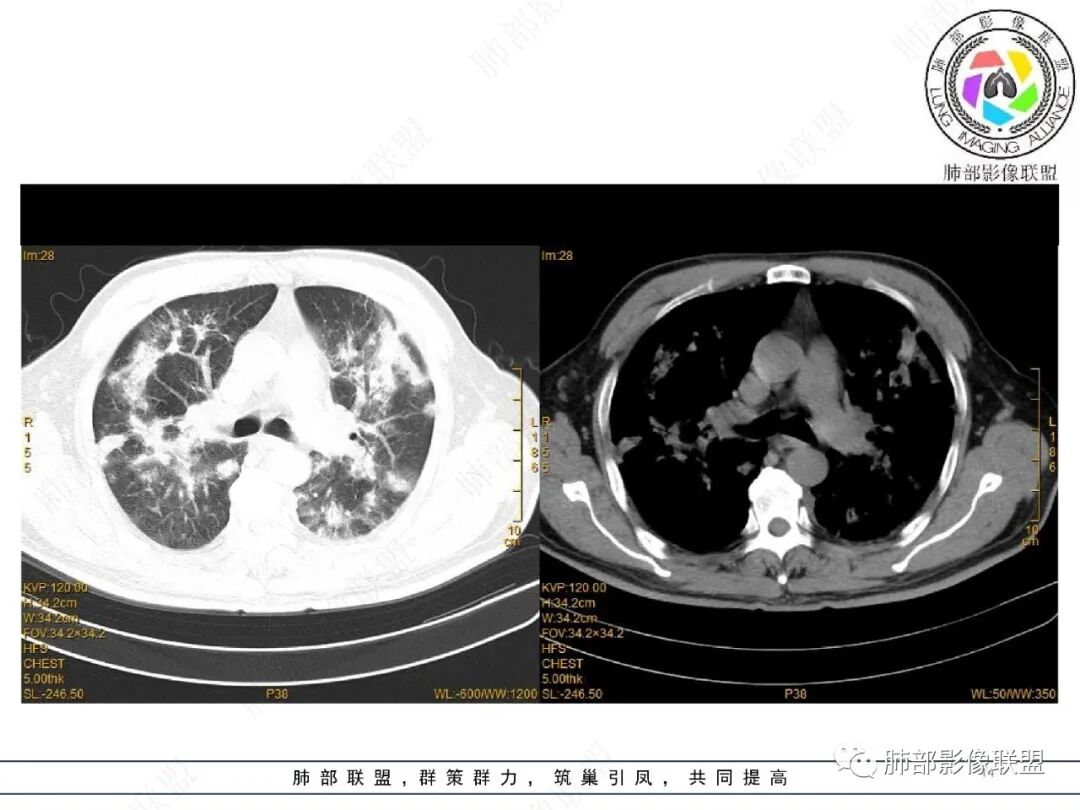

宇宙: 两肺沿支气管血管束及胸膜下分布多发结节、斑片及实变,边缘模糊,右肺病灶可见反晕,复查吸收好转,边界清,考虑OP

谢加平: 两肺叶多发斑片实变影,边缘模糊,沿支气管血管束对称分布,血管束不清,抗髓过氧化酶抗体阳性,支持血管炎表现,治疗后复查双肺病灶较前吸收好转,范围减少,病灶边缘收缩,支气管有牵拉打张,伴随0P肺炎改变。

相对而言:已经融合的,边缘平直、光滑一些,周围纤维化明显一些,没融合的边缘模糊一些,周围GGO多一些;提示融合的病灶更早,已经开始有纤维化改变特点;而没融合的属于后发一些的病灶,纤维成分还不够

至于这种反晕征状:我认为是外周一层的小叶核心病灶与偏内侧的小叶核心病灶的融合,不是大片状病灶周围的修复所指。

2022.2.17CT显示两肺中内带多发结节影、斑片影、条索影,部分病灶侧向融合与胸膜平行。部分病灶沿着支气管血管束分布、其内支气管稍扩张。部分病灶呈反晕征。大部分病灶边界显示清晰,部分病灶周围可见边界不清的GGO。2022.4.12CT显示两肺中内带多发结节影、条索状、条带状高密度影,边界收缩平直凹陷,大部分病灶沿着支气管血管束分布,亦有位于胸膜下侧向融合与胸膜平行的病灶。总体与第一次CT对比两肺病灶明显吸收。